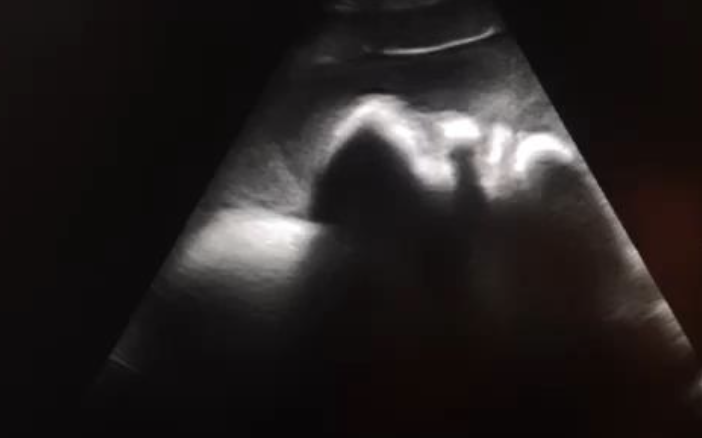

ultrasound: swirling echogenic fluid

2. ultrasound: liver abscess, dilation of CVC